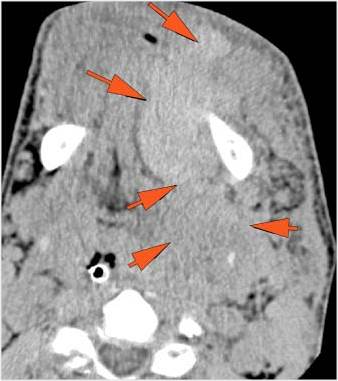

Facial and Scalp Soft Tissues and Airway

There is localized edema, hematoma or abscess within in the facial or scalp soft tissues, SMAS, infratemporal fossa, masticator space or oral cavity. [Yes/No]

There is evidence of gas or a foreign body at a possible fracture site, indicative of an open or penetrating injury. [Yes/No]

There is soft tissue swelling suggesting injury to the parotid or submandibular glands. [Yes/No]

The upper airway is significantly narrowed or obstructed. [Yes/No]